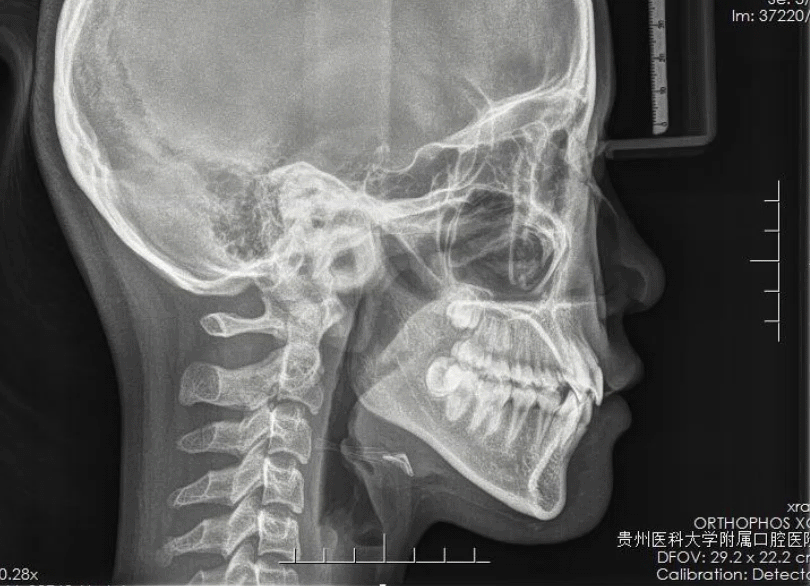

3. X影像:辅助医师了解牙颌、颅面软硬组织的结构,使对牙颌、颅面的检查、诊断由表面形态深入到内部的骨骼结构中去。